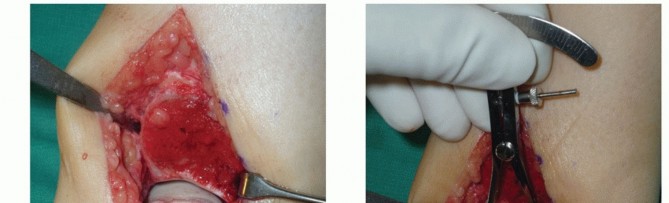

Define the dimensions of the recipient site. Use a caliper and a ruler and double-check the measurements. - Harvesting Graft from Donor Talus

Handle the allograft talus with bone forceps.

Properly orient the talus (compare to native talus) to ensure that the cuts will be congruent and in the same plane as those for the recipient site.

Carefully mark the dimensions for graft harvest on the allograft (TECH FIG 3A).

Same location on the allograft talus as the recipient site on the native talus

If you err, err to have the graft slightly too large. Be sure to account for saw blade thickness. “Measure twice and cut once.”

You have only one opportunity, so be sure the measurements and orientation of the saw blade for each cut are optimal.

The allograft can be stabilized with two large pointed reduction clamps (TECH FIG 3B).

Extract the graft from the donor talus (TECH FIG 3C).

Reduce the immunogenic load from the graft by washing the graft's cancellous surfaces with saline. - Implanting and Securing the Graft into the Recipient Site

- TECH FIG 3 • A. The dimensions of the recipient site are carefully recorded and transferred to the allograft. B. Two pointed reduction clamps are used to stabilize the allograft during preparation. C. Donor allograft with newly prepared graft removed.